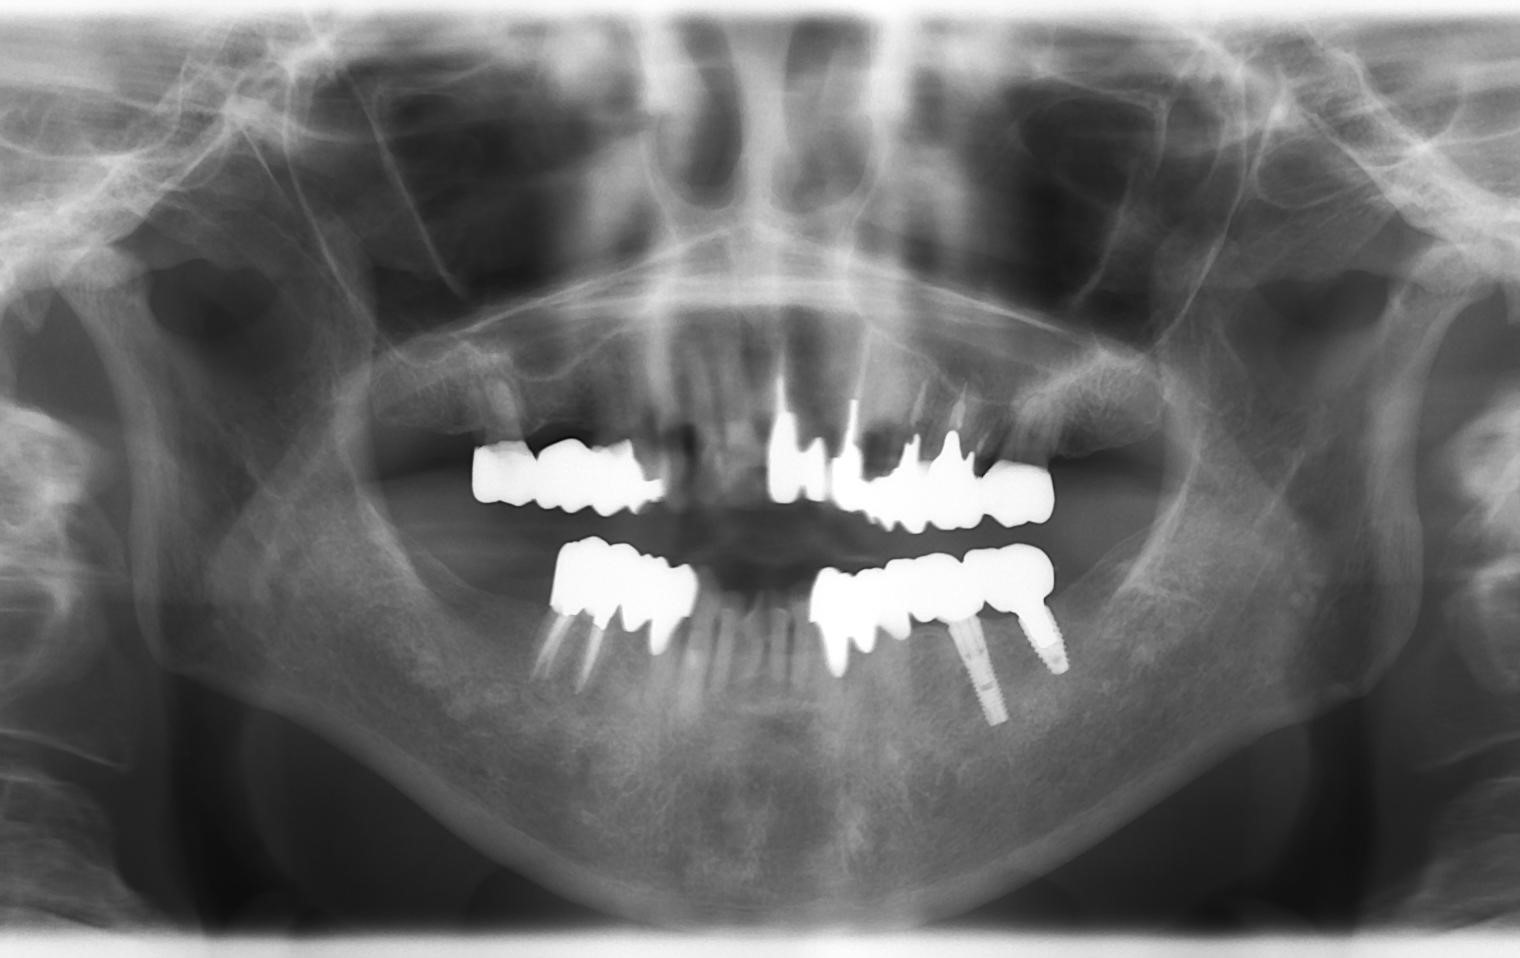

【症例】20年後も健康なインプラント(レントゲン写真)

この方は、約20年前に提携している専門医の歯科医院様からのご紹介で来院されました。「歯の根が割れてしまい、抜歯が必要」との診断を受け、失った歯を補うために当院でインプラント治療を行いました。

下の画像は、治療から20年以上が経過した現在のレントゲン写真です。

▼お口全体のレントゲン写真 赤丸で囲んだ部分が、20年前に治療したインプラントです。